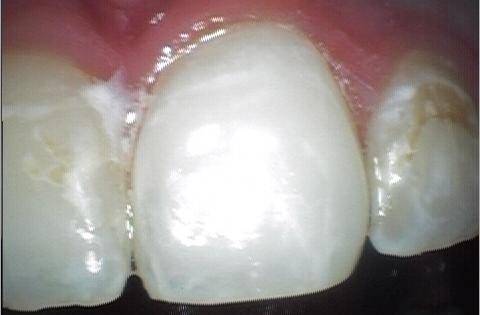

Dr. Terveen will remove the decay in and around your tooth and then restore it using a composite resin filling.

Composite resin fillings are both durable and natural-looking. We'll match the new filling to your tooth’s coloring so they blend together, which means nobody will be able to tell the difference between the two.

With advancements in dental technology and materials, our Colorado Springs dental office can now offer tooth-colored composite resin fillings. Not only do tooth-colored fillings blend in seamlessly with your smile, but they also require less removal of your tooth structure to bond with your tooth.

Our office provides a variety of different filling materials to suit the individual needs of each patient; however, most of these fillings are tooth-colored composite. Composite has many benefits, such as blending naturally with the tooth, bonding to the remaining structure, and acting relatively inert in your mouth.